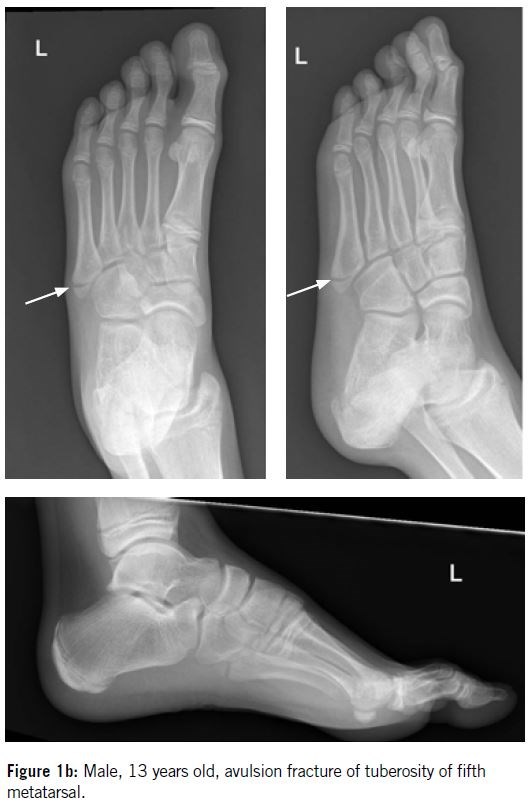

The Lawrence and Botte classification system (Figure 3) is commonly used and holds prognostic value based on fracture zone distributions. The proximal fifth metatarsal is divided into three zones:

Zone l / tuberosity (Figure 4)

Zone II / metaphyseal - diaphyseal junction   (Figure 5)

Zone III / proximal diaphysis

Fractures in zones II and III have poor vascularization and higher complications rate.